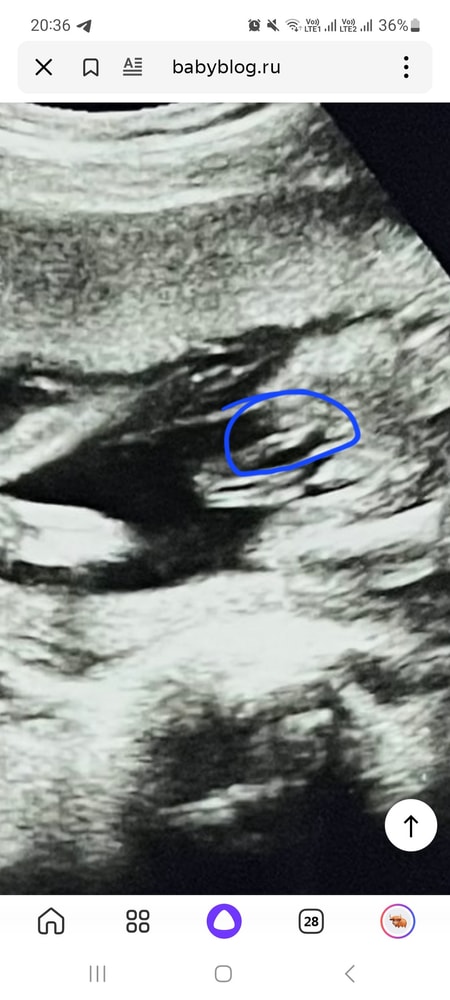

Ariana Kravchenko, видео что это идёт продолжение ноги, кости. Соответственно чуть выше над вашим обеденным идёт писюн. А вот там под другим ракурсом надо посмотреть)

Ирина , пригляделась и увидела будто бы яички и выпуклость маленькую))